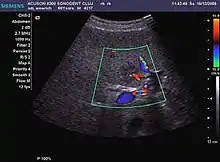

It is a tumor developed secondary to a circulatory abnormality with abundant arterial vessels having a characteristic location in the center of the tumor, within a fibrotic scar. A radial vessels network develops from this level with peripheral orientation. The tumor's circulatory bed is rich in microcirculatory and portal venous elements. The incidence is higher in younger women and tumor development is accelerated by oral contraceptives intake. 2D ultrasound appearance is a fairly well-defined mass, with variable sizes, usually single, solid consistency with inhomogeneous structure. Rarely the central scar can be distinguished. Spectral Doppler examination detects central arterial vessels and CFM exploration reveals their radial position. CEUS examination shows central tumor filling of the circulatory bed during arterial phase and completely enhancement during portal venous phase. During this phase the center of the lesion becomes hypoechoic, enhancing the tumor scar. During the late phase the tumor remains isoechoic to the liver, which strengthens the diagnosis of benign lesion.